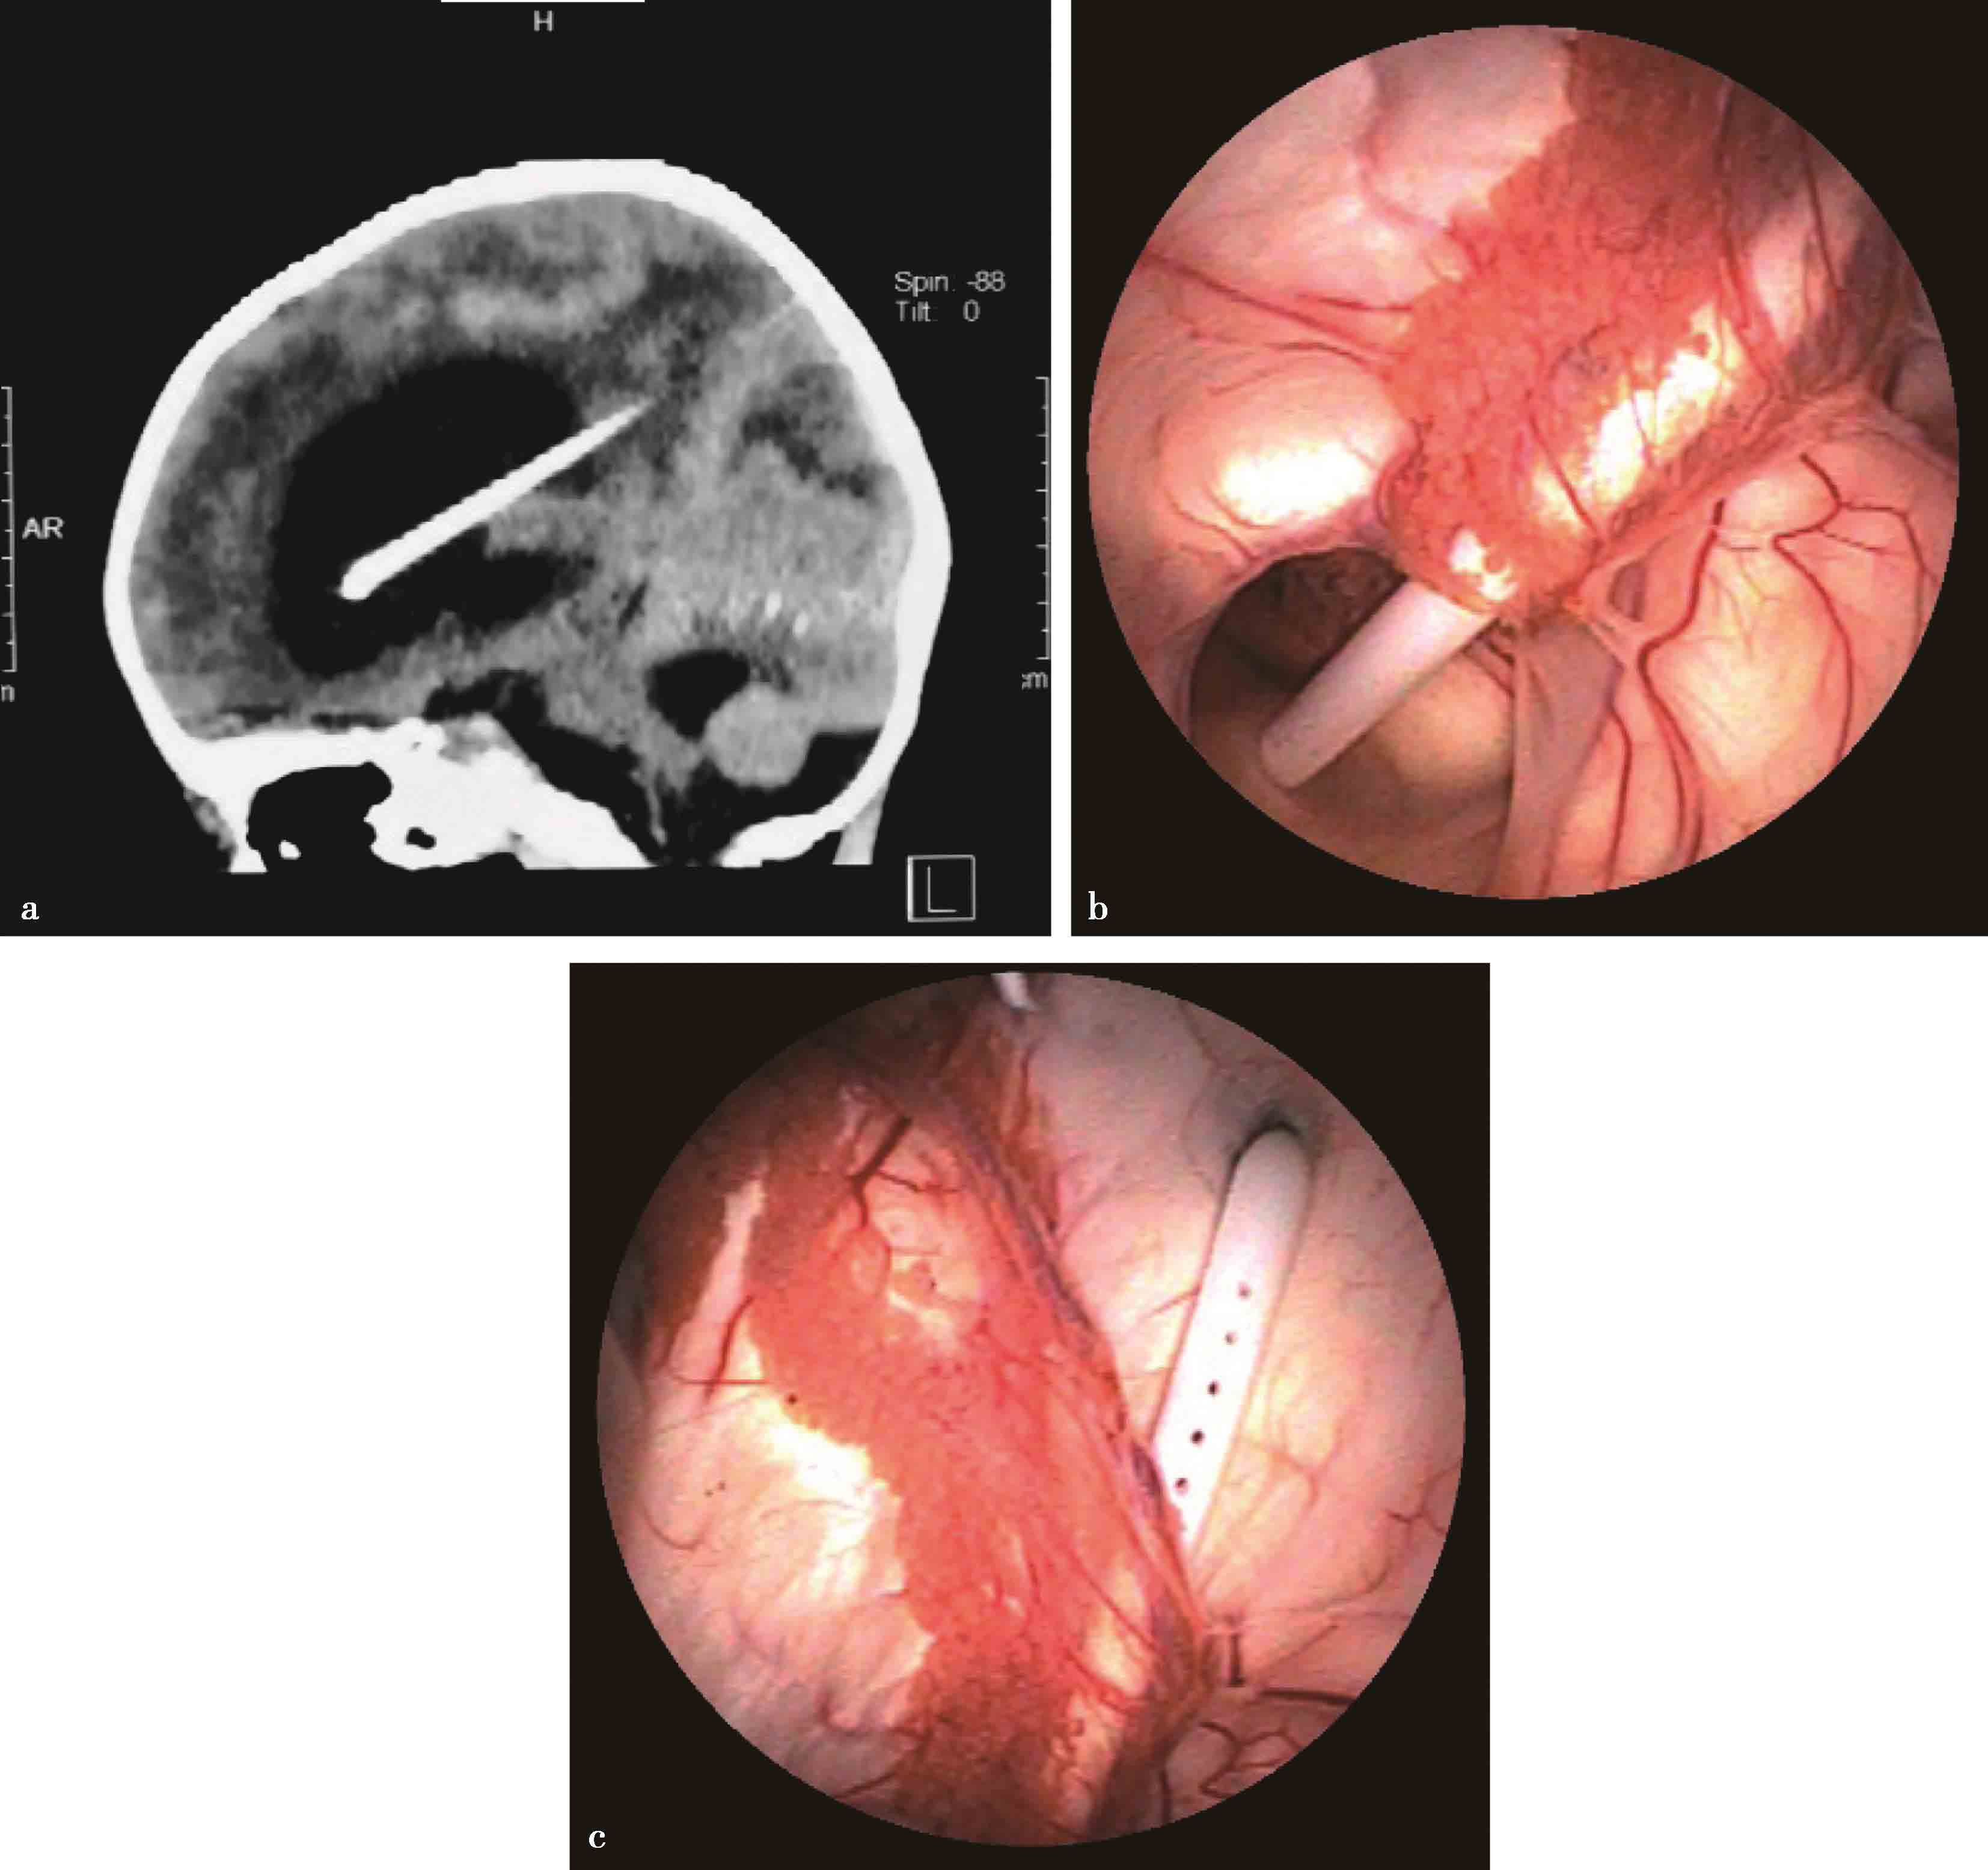

图3-1-1-1 出血后脑积水的脑室演变

a.发病时头颅CT:脑室内血肿呈高密度;b.发病12天后复查CT:血肿已呈低密度;c.发病5个月后头颅MRI:脑室明显扩张,脑室内未见异常信号;d.内镜下探查见脑室内仍有陈旧血斑及含铁血黄素沉积